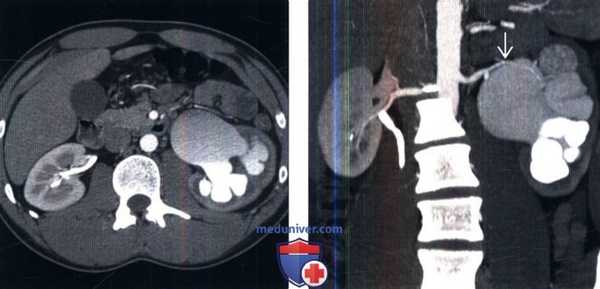

(Слева) На рисунке представлена врожденная обструкция пиелоуретерального сегмента с резким сужением и угловой деформацией пиелоуретерального сегмента, ставшими причинами пиелокаликоэктазии и умеренной атрофии коркового вещества.

(Справа) Контрастная КТ, аксиальная проекция: обнаружены расширенная почечная лоханка, каликоэктазия и атрофия паренхимы правой почки, предположительно связанные с врожденной обструкцией пиелоуретерального сегмента, которая никогда не подвергалась лечению. Для сравнения: в левой почке выявлена экстраренальная почечная лоханка. Обратите внимание на отсутствие каликоэктазии или повреждений почечной паренхимы. (Слева) Контрастная КТ, аксиальная проекция: у пациента с двусторонней обструкцией пиелоуретерального сегмента обнаружены двусторонний гидронефроз и атрофия коркового вещества с контрастированной мочой в нижних частях расширенных чашечек. Мочеточники нормального калибра, без вызывающих обструкцию объемных образований или других аномалий.

(Справа) При рентгенографии в вертикальной проекции у данного пациента с 30-минутной задержкой после контрастной КТ обнаружены двусторонняя пиелокаликоэктазия и замедленный клиренс контрастного вещества из собирательной системы. Мочеточники нормального калибра визуализированы плохо.